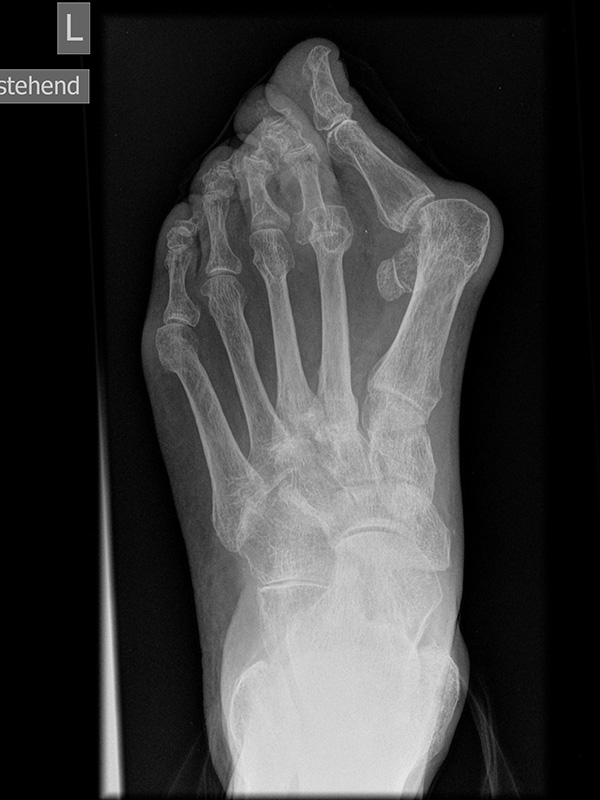

Fuß dp (dorsoplantar) mit Belastung

Positionierung:

• Der Patient steht unter gleichmäßiger Gewichtsbelastung auf beiden Füßen.

• Die Fußachse ist nach vorne gerichtet.

• Die Kassette liegt unter dem zu röntgenden Fuß.

• Der Zentralstrahl wird auf das Tarsometatarsalgelenk II zentriert.

• Die Röntgenröhre ist 15° vertikal gekippt.

• Anmerkung: Technisch lässt sich die Röhre beim stehenden Patienten nicht in 0° über dem Fuß positionieren. Eine Kippung der Röhre um 15° erlaubt darüber hinaus eine bessere Einsicht in die tarsometatarsalen Gelenke.

Kennzeichen des Röntgenbildes:

• Standardabbildung des Fußes zusammen mit der belasteten seitlichen Aufnahme und der unbelasteten Schrägaufnahme.

• Die belasteten Aufnahmen liefern relevante Informationen zur Fußstatik und sind die Grundlage aller achskorrigierenden Eingriffe an Vor- und Rückfuß.

• Sämtliche Winkelbestimmungen beziehen sich auf belastete Aufnahmen.

Besondere Bemerkungen zum Beispielbild:

• Schwere Hallux valgus Deformität.

• Die Sesambeine sind luxiert, ebenso das Großzehengrundgelenk. Luxation des Metatarsophalangealgelenks II.

• Degenerative Veränderungen der tarsometatarsalen (TMT) Gelenkreihe, betont TMT II und III.

Zur Vollansicht und zum Lesen der Bildbeschreibung bitte die Bilder anklicken.